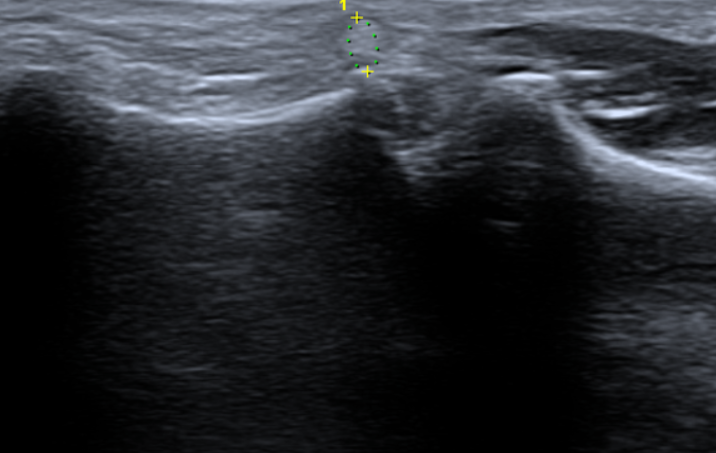

엄지손가락이랑 손바닥 이어지는 사이에 혹같은게 생겼습니다 크기는 크지않은데 움직일때 아프도라고요 1차병원에서는 상급병원으로 가라고 해서 3차 병원 성형외과 수부쪽으로 다녀왔는데 크기로는 결절종인것같다고 근데 초음파를 정확하게 찍어봐야안다 자긴 잘 모른다면서(판독지 없었음) 초음파를 한번 더 찍으라네요 결절종이면 3차 아니어도 1차나 2차병원에서 일단은 주사로도 해결 가능한 부분이니 다시 2차병원으로 갈 예정인데 보기엔 어때보이시나요?

• 1번 째 사진